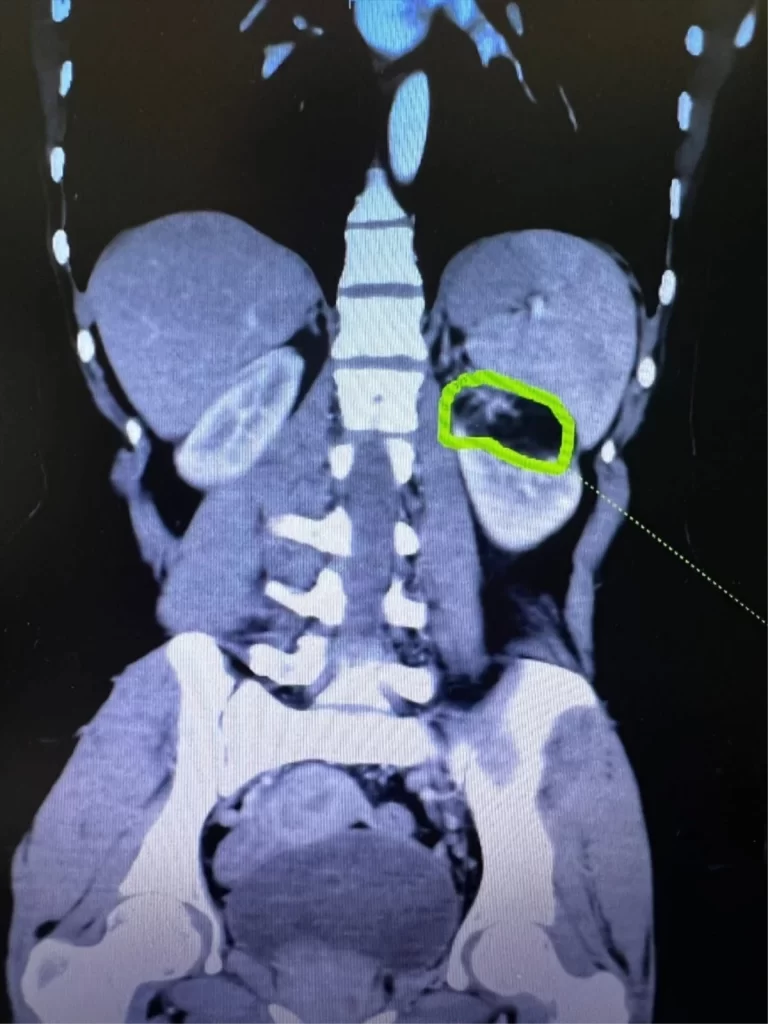

Gaziantep’te ileri derece obez olan 58 yaşındaki hastanın sağ böbreğindeki kanserli kitle ameliyatla alındı.25 Aralık Devlet Hastanesinden yapılan açıklamada,58 yaşındaki ileri derece obez hastanın sağ böbreğindeki kitlenin Üroloji Uzmanı Op. Dr. Mehmet Öztürk tarafından alındığı belirtildi.Ameliyatın başarılı geçtiği ve hastanın sağlığına kavuştuğu aktarılan açıklamada, şunlar kaydedildi: “Riskli vakalardan bir diğeri de sol böbrekteki 6 cm’lik kitleye bağlı kanama olasılığından dolayı gebeliği sonlandırılmış E.S’ye başarılı geçen operasyonla böbrek koruyucu kanser ameliyatı yapılarak böbreğe zarar vermeden kanserli doku çıkarılmıştır. Operasyon sonrası yapılan takiplerinde sağlık durumu iyi olan hasta 3. günü taburcu edilmiştir. Ayrıca bir diğer vakada 78 yaşındaki kadın hastaya, sol böbrekte 3 cm kitle nedeniyle sol oparsiyel nefrektomi ameliyatı da ekibimiz tarafından başarılı bir şekilde uygulanmıştır.”Tümörün boyutu ve yerleşimi nedeniyle böbrek koruyucu cerrahi imkanı olmayan hastalara benzer ameliyatların başarılı ile gerçekleştirilerek sonuç alındığı ifade edildi.Kaynak: AA / Güncel Mehmet Öztürk Gaziantep Aralık Sağlık Güncel Haberler

Gaziantep’te ileri derece obez hastanın böbreğindeki kanserli kitle ameliyatla alındı